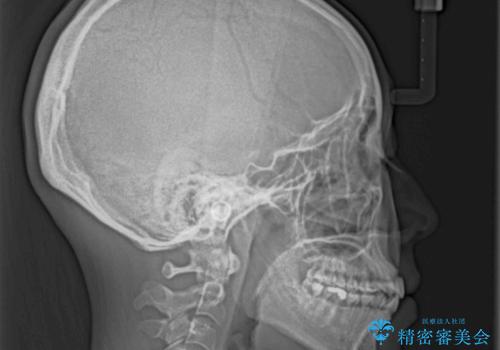

- 前歯がデコボコした上に口元が閉じにくいことを気にして来院された患者様です。

IPR(歯と歯の間を削る)と側方拡大では口の閉じにくさは改善できそうになく、一方で抜歯矯正を行うほどの突出感は認められませんでした。

親知らずを全て抜去し、歯列全体を後方に移動させることで口元の閉じにくさいを改善していくこととしました。